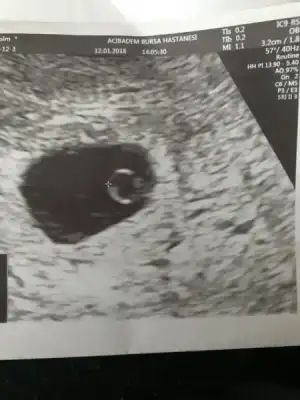

Ara canım mutlaka,vajinal kullanmak çok daha rahat. Dün sana kese fotosu koyacaktım dışardayım diye koyamadım. Şimdi koyayım bak. 1. Foto kesenin ilk hali, 2. Foto fasulyeye dönmüş hali.

Ben Eskişehir Acıbademde yaptırıcam takip ve doğumumu. Burada aşılamamı yapan doktorum var ona gidicem. 120 tl idi aralıkta zam gelmiştir ocakta sezeryan doğumda 5000 tl imiş sanırım. İlk muayene için tüp bebek yaptırdığım Bursa Acıbademdeki dr çağırdı ilk muayene tedavi ücretine dahil değilmiş orada 350 tl vericez sonra burada devam